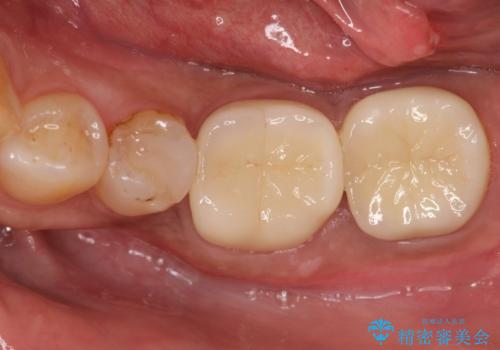

以前治療した歯が痛む 銀歯をセラミックに